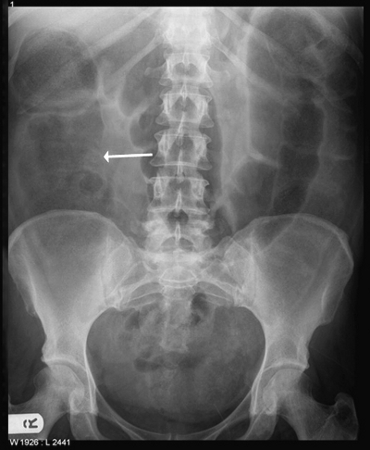

Large bowel obstruction

Large bowel obstruction. Plain radiograph showing distended large bowel loops. Note grossly dilated caecum (white arrow)

Musson RE, Bickle I, Vijay RKP, et al. Gas patterns on plain abdominal radiographs: a pictorial review. Postgrad Med J. 2011 Apr;87(1026):274-87; used with permission